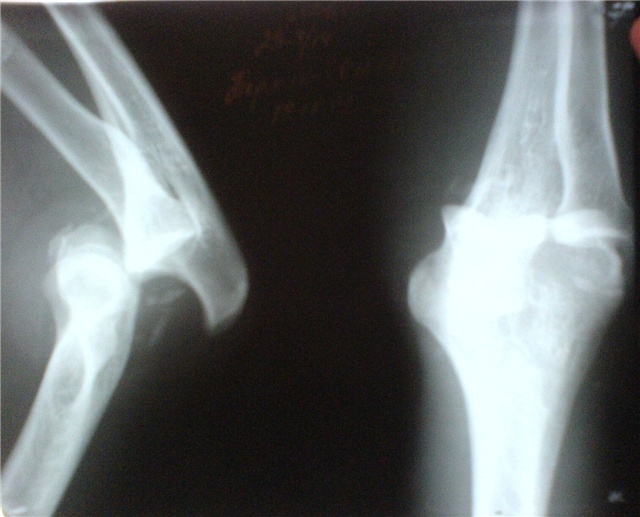

Вывих локтевого сустава (рентгенограмма)

Вывихом локтя называется смещение двух основных костей предплечья из места сочленения с нижним концом плечевой кости. Локтевой сустав является местом, где сходятся три вышеуказанные кости. Вывих данной локализации встречается редко.

После вправления обязательно проведут рентген-диагностику руки и закрепят локтевой сустав шиной или давящей повязкой. Зафиксированная рука будет в форме перевернутой буквы «Г» некоторое время. Обычно фиксация проводится с помощью гипса, но в последнее время современные клиники применяют медицинское стекловолокно. Обездвиживание проводится с целью исключить движение в локтевом суставе. Загипсованная рука подвязывается к плечу, чтоб человеку было легче поддерживать верхнюю конечность на одном уровне.